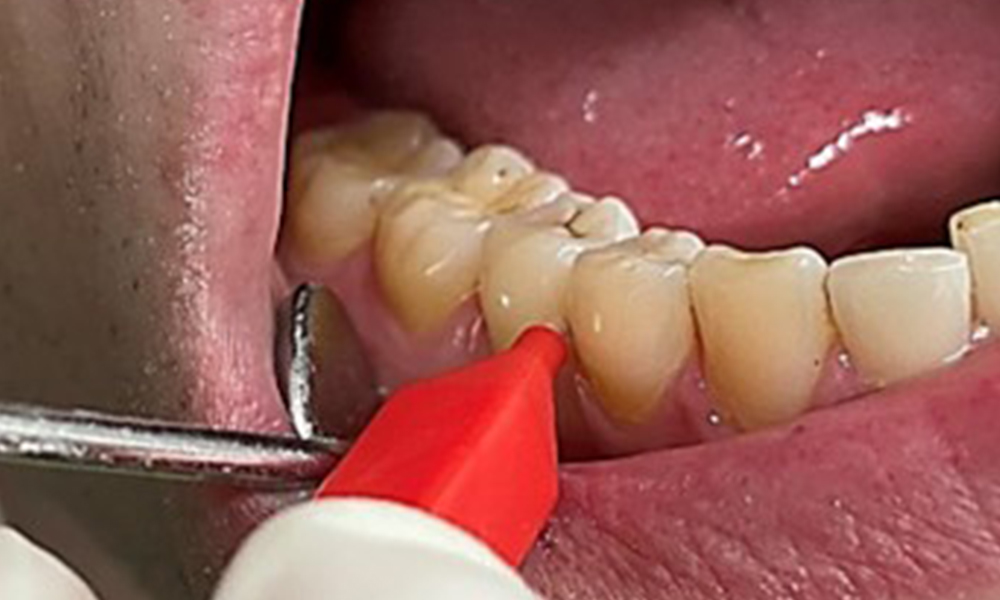

Due to the otherwise favourable general medical condition, the needs determined during the intraoral examination will be decisive for their treatment. It will be essential to periodically determine the probing depths. Gingival bleeding decreases in smokers, which is why the clinical diagnosis of periodontitis can only be made by probing (Fig. 7). Placing exclusive focus on the determination of bleeding indices may obscure existing periodontitis or gingivitis. (5)

Pocket probing (BOP) with depiction of tooth 36 lingual

Fig. 7 Pocket probing (BOP) with depiction of tooth 36 lingual, © Dr R. Krapf